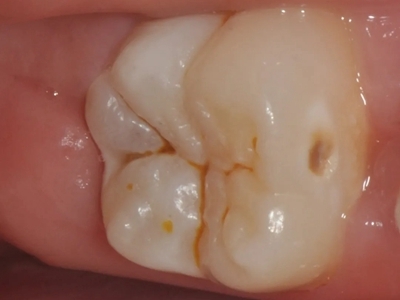

年轻恒牙龋指的是儿童萌出不久的第一恒磨牙龋病和上颌恒切牙龋病,其中第一恒磨牙龋病占年轻恒牙龋的90%,发病早,进展快,可表现为白垩色斑片、点隙窝沟墨浸状龋坏或龋洞。本病的发生和年轻恒牙的特点以及儿童饮食、口腔卫生等因素有关。

年轻恒牙龋好发于第一、二恒磨牙(牙合)面、邻面,上颌中切牙邻面,多为急性龋,龋坏进展快。平滑面的早期龋多为白垩色的斑片,点隙窝沟的早期龋多为浸墨状,表面粗糙。如果早期龋不及时治疗,可逐渐形成大而深的龋洞,易导致牙髓炎和根尖周炎。